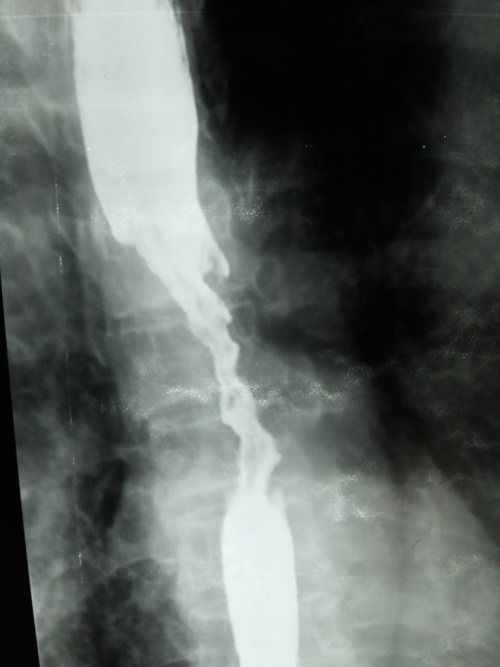

Oesophageal cancer

Until recent times oesophageal cancer was most commonly due to a squamous cell carcinoma but the incidence of adenocarcinoma is rising rapidly. Adenocarcinoma is now the most common type of oesophageal cancer and is more likely to develop in patients with a history of gastro-oesophageal reflux disease (GORD) or Barrett's.

The majority of adenocarcinomas are located near the gastroesophageal junction whereas squamous cell tumours are most commonly found in the upper two-thirds of the oesophagus.

Features

- dysphagia: the most common presenting symptom